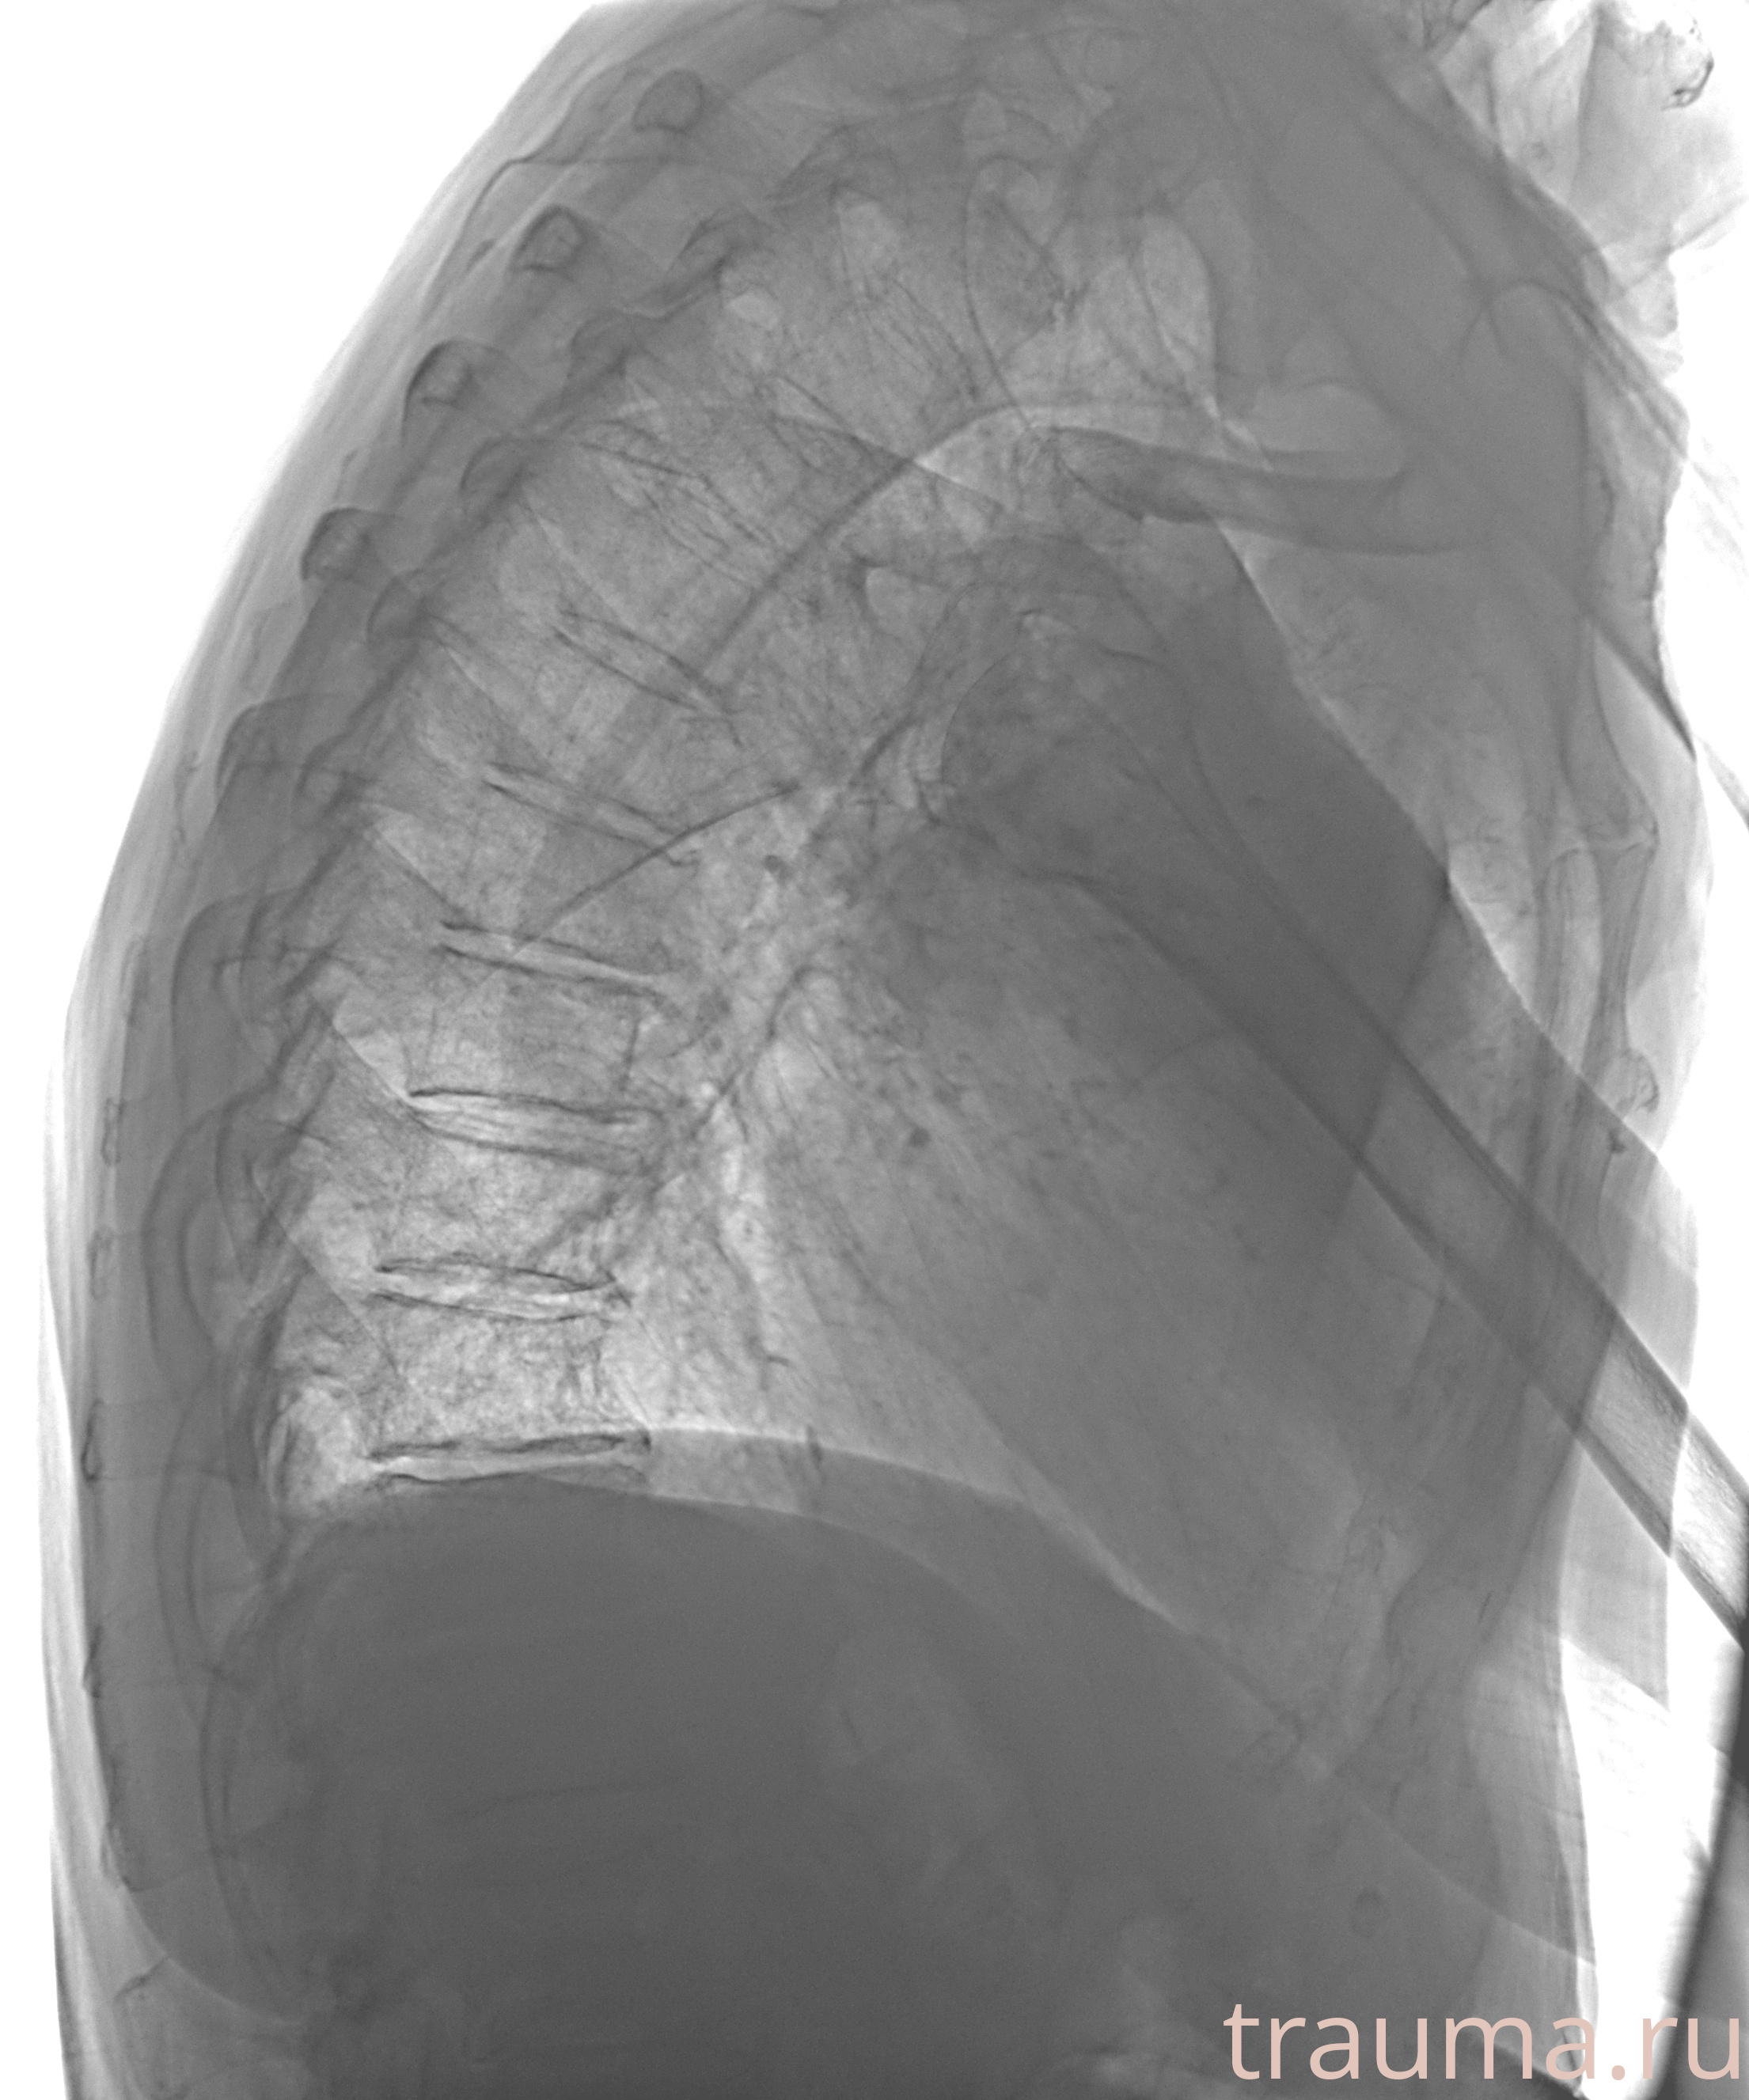

Рентген на дому: по вашему адресу приезжает врач-рентгенолог, травматолог-ортопед с мобильным рентгеновским аппаратом, проводит диагностику травмы или заболевания, делает необходимые рентгенограммы, дает рекомендации по дальнейшему лечению. Получить качественные снимки в домашних условиях возможно благодаря уникальной методике, разработанной МосРентген Центром для института  Склифосовского